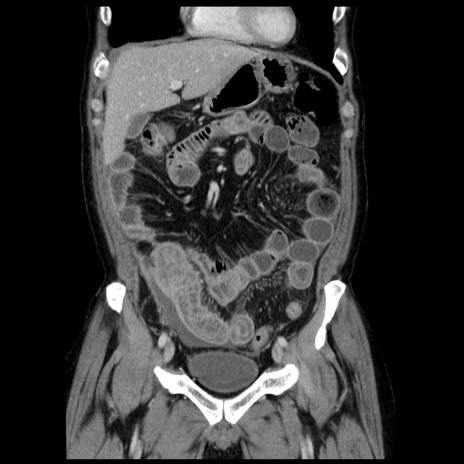

横断像

【症例】40歳代男性

【現病歴】2日前から胃痛あり。徐々に周期的な激痛に変化した。本日になっても激痛があるため受診。

【身体所見】意識清明、BT 38-39℃台あり、腹部:膨満、やや硬、右下腹部に圧痛あり。

【データ】WBC 8500、CRP 23.26